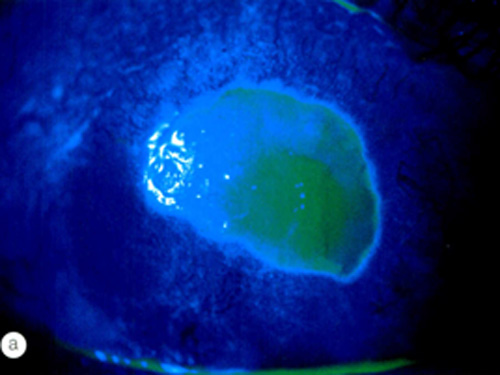

It is a condition where the surface layer of the cornea (the epithelium) automatically detaches from the underlying membrane (basement membrane). This occurs due to defective adhesion between the layers, making the cornea vulnerable even to friction of the eyelids upon waking.

2. Invasive Techniques: * Surface Scraping: Removal of the loose epithelium to grow new, healthy epithelium.